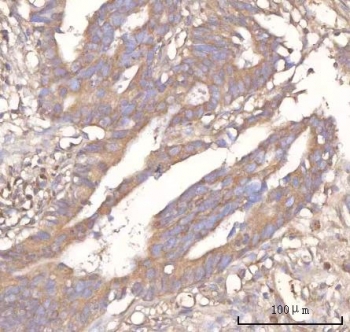

IHC staining of FFPE human rectum adenocarcinoma tissue with Neuralized-like protein 4 antibody. HIER: boil tissue sections in pH8 EDTA for 20 min and allow to cool before testing.